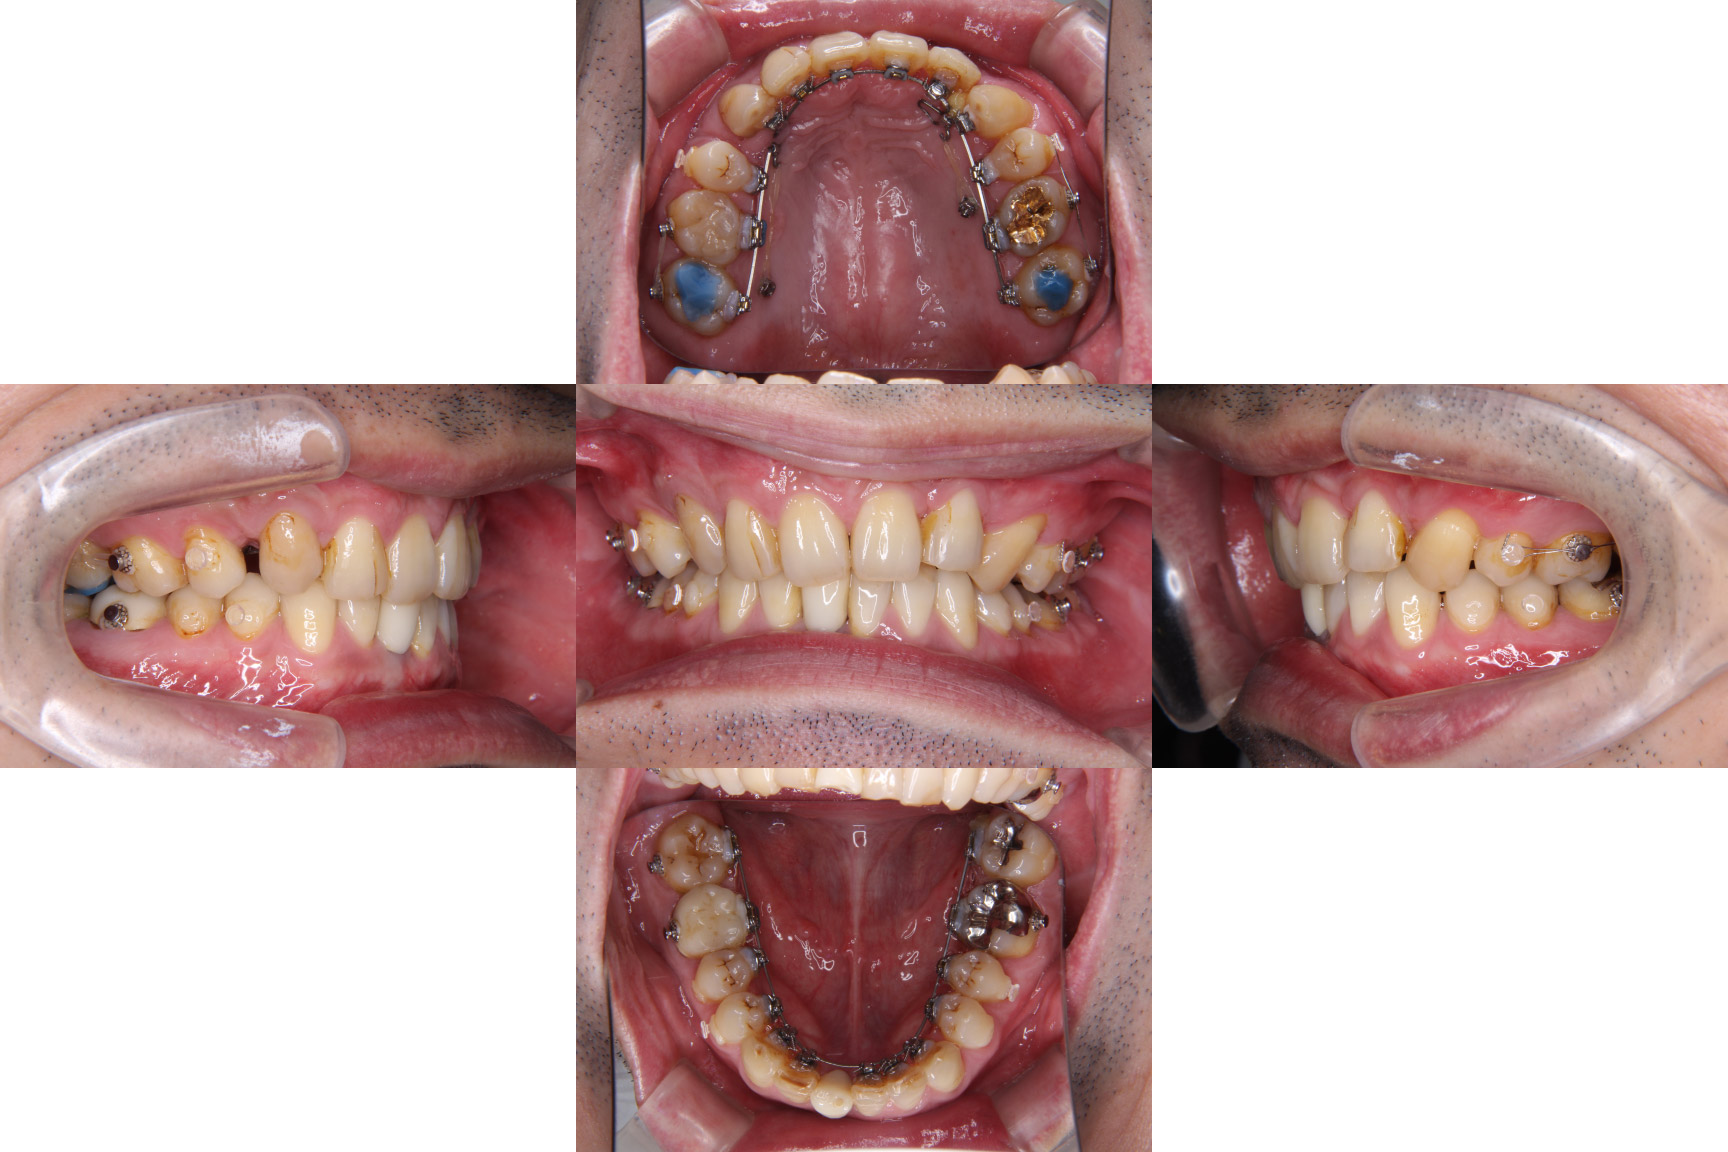

| 主訴 | 【主訴】ディープバイト,すきっ歯 【診断・症状】左上C残存、下顎右下1番欠損、上顎前突、空隙歯列、過蓋咬合 |

| 治療期間 | 約3年半(45回) |

| 矯正の装置 | 裏側矯正(舌側矯正) |